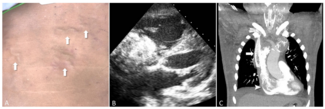

A 55-year-old Thai man with history of chronic alcoholism presented to our hospital complaining of sudden onset of severe substernal chest pain and profuse sweating for 4 hours. Upon arrival, he was barely conscious. His initial blood...